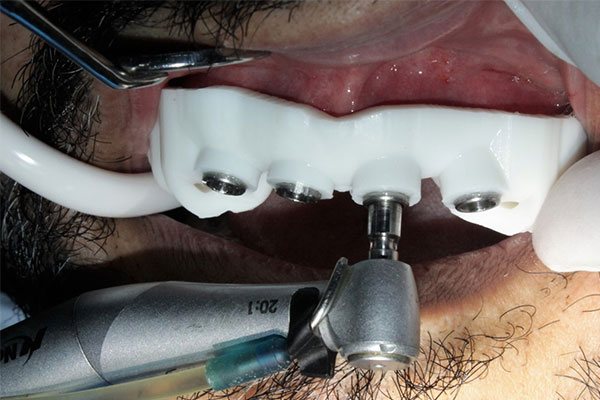

The Surgical Guide is designed and printed with 3D technology. Everything is done in-house at our Clinic. The Guide itself is made based on 3D Imaging and is very accurate. Small offset pieces are placed to assure that the dentist does not drill too far, or at an unfavorable angle. This is very helpful during the restorative phase of your Implants.